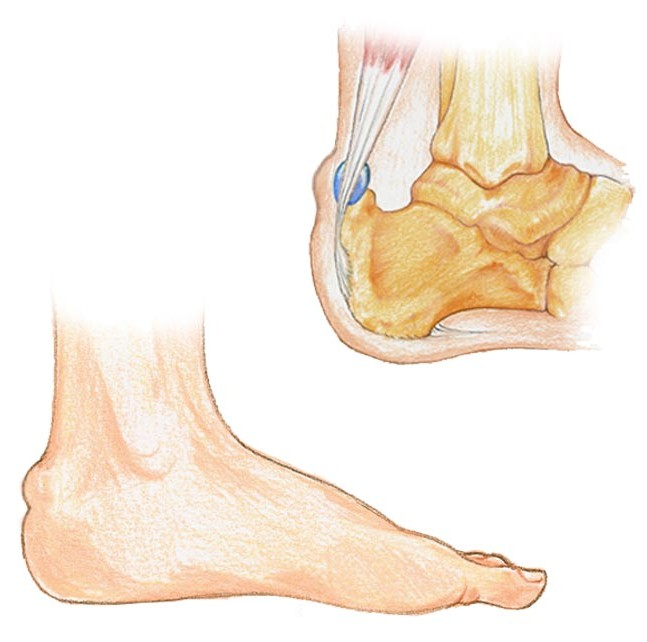

If you are suffering from Haglund’s deformity you will most likely have noticed a bony enlargement at the back of the heel. This inflammation is caused when the soft tissue around the Achilles tendon becomes irritated. Irritation at this particular spot is often the result of pressure caused by the back of pump-style shoes. Other signs of Haglund’s deformity include pain in the back of the heel, where the Achilles tendon and the heel meet, swelling in the back of the heel and redness or inflamed tissue at the site of the swelling.